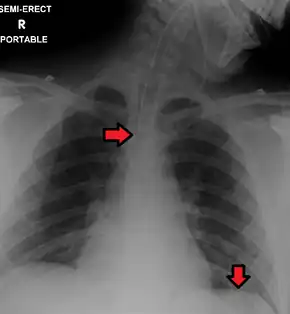

In anteroposterior (AP) views, the positions of the x-ray source and detector are reversed: the x-ray beam enters through the anterior aspect and exits through the posterior aspect of the chest. AP chest x-rays are harder to read than PA x-rays and are therefore generally reserved for situations where it is difficult for the patient to get an ordinary chest x-ray, such as when the patient is bedridden. In this situation, mobile X-ray equipment is used to obtain a lying down chest x-ray (known as a "supine film"). As a result, most supine films are also AP.